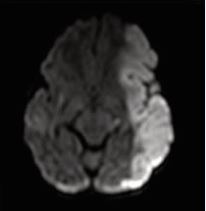

The presence of abnormal neurologic symptoms in the examined 79 infants was observed at the following ages: 9 in the delivery room; 21 during the first 24 hours; 15 during the first or second day of life; 13 at the first or second week; 21 infants showed their first symptoms during the 3rd or 4th month. Examining the Apgar score, 31 out of 79 infants had 9/10 or 10/10, 20 had 8/9 or 9/9, and 28 had an extremely low as 0/0/4 up to 6/7.In 25 patients no abnormal neurological signs were observed during the whole study, including the follow up. Seizures were observed in 50 infants as their first sign (Figure 2), but 8 also had apnea, irritability, and opisthotonic spasms. Neurosonography was performed in all infants, MRI [10], in 77 infants, CAT scan in 1, and no MRI/CAT in 1. Figures 3a, 3b, and 4 show some examples of the lesions.

Figure 3b MCA stroke on the left (a) and right side (b).

https://www.jscimedcentral.com/public/assets/images/uploads/image-1762766315-1.JPG